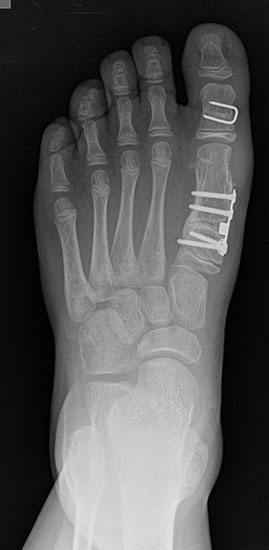

Bezüglich der Operationstechniken wird von früher häufig durchgeführten alleinigen Weich­teileingriffen am Großzehengrundgelenk aufgrund hoher Rezidivraten abgeraten 15. Die Operation nach Mc Bride mit lateralem Release, Exzision des lateralen Sesambeins, Abtragen der Pseudoexostose, Sehnenetransfer des M. adductor hallucis und mediale Kapselraffung zeigte unbefriedigende Mittel- und Langzeitergebnisse 16. Die Cerclage fibreux (mediale Kapselraffung) und das laterale Kapselrelease wird heute in Kombination mit einem knöchernen Eingriff angewendet. Bezüglich des Einsatzes von minimalinvasiven Operations­techniken vor Wachstumsabschluss liegen bisher keine Daten vor. Alle Osteotomien lassen sich nach Bedarf miteinander kombinieren. Es ist darauf zu achten, dass Osteotomien keine offenen Wachstumsfugen verletzen.

• Medial zuklappende Grundphalanxosteotomie nach Akin 17

• Subcapitale distale Chevron Osteotomie nach Austin 18

• Diaphysäre Osteotomie

• Scarf 19

• Ludloff 20

• Proximale Metatarsale I Osteotomien 21

• medial aufklappend – verlängernd

• lateral zuklappend – verkürzend

• bogenförmige Crescentic Osteotomie

• proximale Chevron Osteotomie

• proximale Verschiebeosteotomie

• medial aufklappende Cuneiforme I Osteotomie 1522

• Wachstumslenkung: Hemiepiphysiodese der lateralen Basisfuge am Metatarsale I  23

• Nach Schluss der Wachstumsfugen: TMT I Arthrodese nach Lapidus 2425